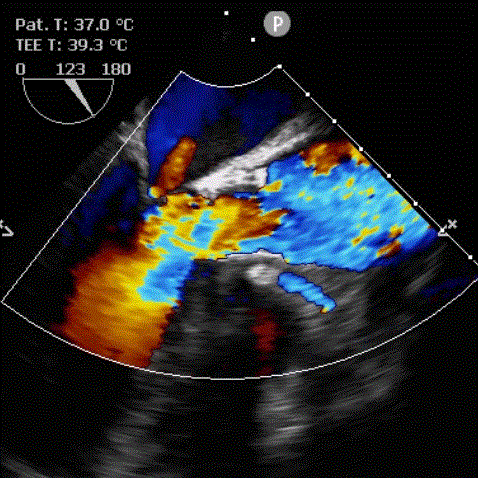

9月27日上午10时,直播开始,魏来教授团队耗时约1小时,经右侧股动脉植入23# Renatus介入主动脉瓣。瓣膜植入位置理想,功能表现出色,造影及经食道超声观察显示瓣膜无中央性返流,轻微瓣周漏,无冠脉血流受阻,无传导阻滞,主动脉瓣峰值流速降至2.0m/s,平均跨瓣压差降至7mm/Hg。手术取得圆满成功。

术后经食道超声